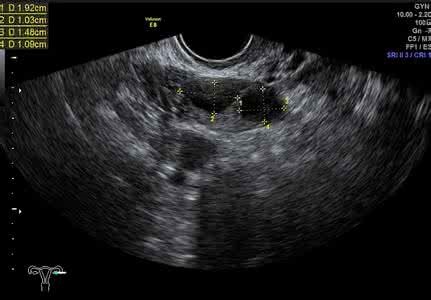

2.超声检测——基础窦卵泡数、卵巢体积

窦卵泡计数能帮助我们估计卵巢储备情况,药物刺激卵巢的响应,以及判断体外受精怀孕的成功率。说白点就是,医生在评估病情、分析用药和指导运用辅助生殖技术都要用到。

基础窦卵泡数(AFC)是早卵泡期阴道超声下检测到的直径2-9mm的窦卵泡数目,一般以AFC<5个提示卵巢储备降低,妊娠率下降;AFC6-10个时预示卵巢反应正常;AFC>15个时,预示卵巢高反应,卵泡刺激征(OHSS)的发生率较高卵巢体积大小同样反映了卵巢的功能,通常体积>3cm3 提示卵巢反应性好。超声检查同样不受月经周期的影响,但是以早卵泡期(即月经第2-5天)检查更为准确。